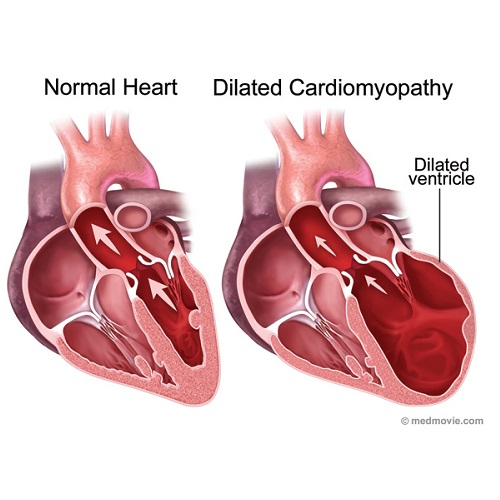

Heart Arrhythmia: Causes, Risk Factors, Symptoms, Treatment

continentalhospitals.comHeart arrhythmia: Causes, Risk Factors, Symptoms, Treatment

continentalhospitals.comHeart arrhythmia: Causes, Risk Factors, Symptoms, Treatment

Cardiovascular Disease: Types, Signs, Prevention, & Causes

www.healthwebmagazine.comCardiovascular Disease: Types, Signs, Prevention, & Causes

www.healthwebmagazine.comCardiovascular Disease: Types, Signs, Prevention, & Causes

Heart Arrhythmias - Physiopedia

www.physio-pedia.comHeart Arrhythmias - Physiopedia

www.physio-pedia.comHeart Arrhythmias - Physiopedia